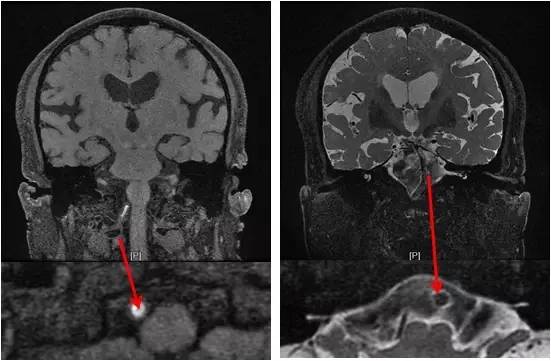

患者一个月前劳累后出现头晕,间断发作,每次持续约5-6分钟,可自行缓解。初未引起重视。其后因症状反复且程度加重,当地医院就诊,行MR提示桥脑及左侧小脑有新发梗死灶(图1)。

图1

MRA:基底动脉中远段重度狭窄,右后交通动脉开放,左胚胎型大脑后动脉,双颈内动脉颅内段及双大脑中动脉多发轻-中度狭窄(图2)。

图2